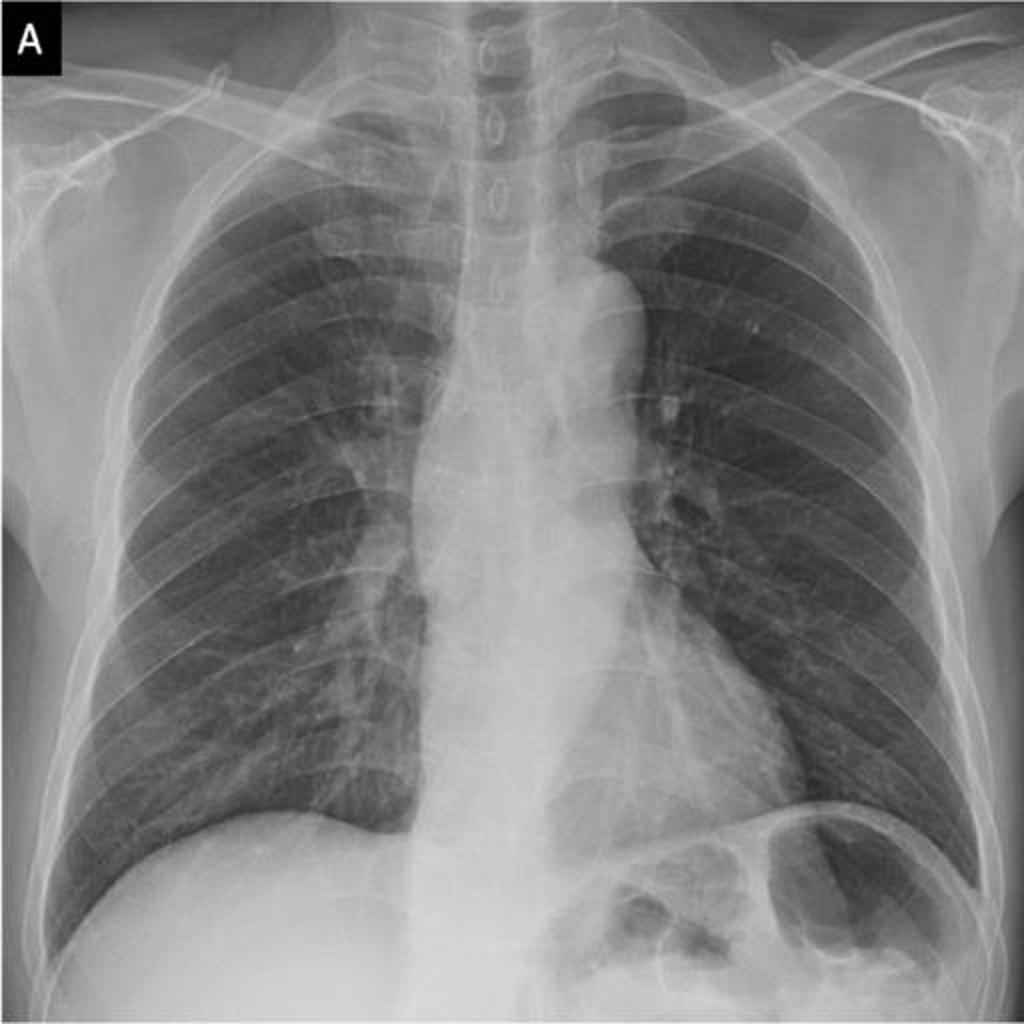

In this project ,we aim to propose a fully-automated method to detect/screen COVID-19 from the patient’s chest X-ray scanned images with out needing a clinical technician.

This is a demonstration of a cloud based AI Web Application which helps medical professionals or diagnostic centers to quickly screen/diagnoise the patient in just a single click.

I've teamed up with AI enthusiasts and got inspired from the several news articles to create a end to end web application using Deep learning.We have collected datasets from Mendeley and Qatar University which were posted on kaggle website.We augumented the images and trained the model to detect the hidden patterns in the images and using "Transfer Learning" approach we have used the model to deploy it on cloud platform and hooked it via flask server.